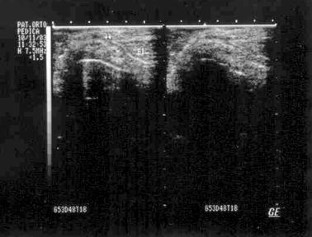

Multilobulated popliteal cyst after a failed total knee arthroplasty

Popliteal cyst is a rare finding after total knee arthroplasty (TKA), but when present, it might indicate a malfunction of the TKA related to generation of wear-particles, or loosening. We present a case of a multilobulated popliteal cyst developing in a patient 8 years after primary TKA. The cyst was associated with a mechanical prosthetic loosening. The primary complaint of the patient was pain in the posterior region of the knee. A two-stage procedure consisting of cyst excision at first, followed after 5 months by a revision TKA was performed. Intraoperatively, a darkish, multilobulated cyst with a well-defined thick wall filled with fluid containing polyethylene debris, communicating with the knee joint was found. After 3 years of follow-up, the patient was satisfied and walked without the support of a cane. The patient presented a satisfactory knee range of motion. Clinical, radiological and ultrasound investigations ruled out popliteal cyst recurrence. A dissecting popliteal cyst associated with a failed TKA should be excised because it contains polyethylene debris that constitutes an induced factor for prosthetic loosening. A two-stage procedure with quite a long time in-between, as presented in this paper, can be a useful alternative to manage such a problem, in particular in very old patients associated with other medical problems.

Fig. 3